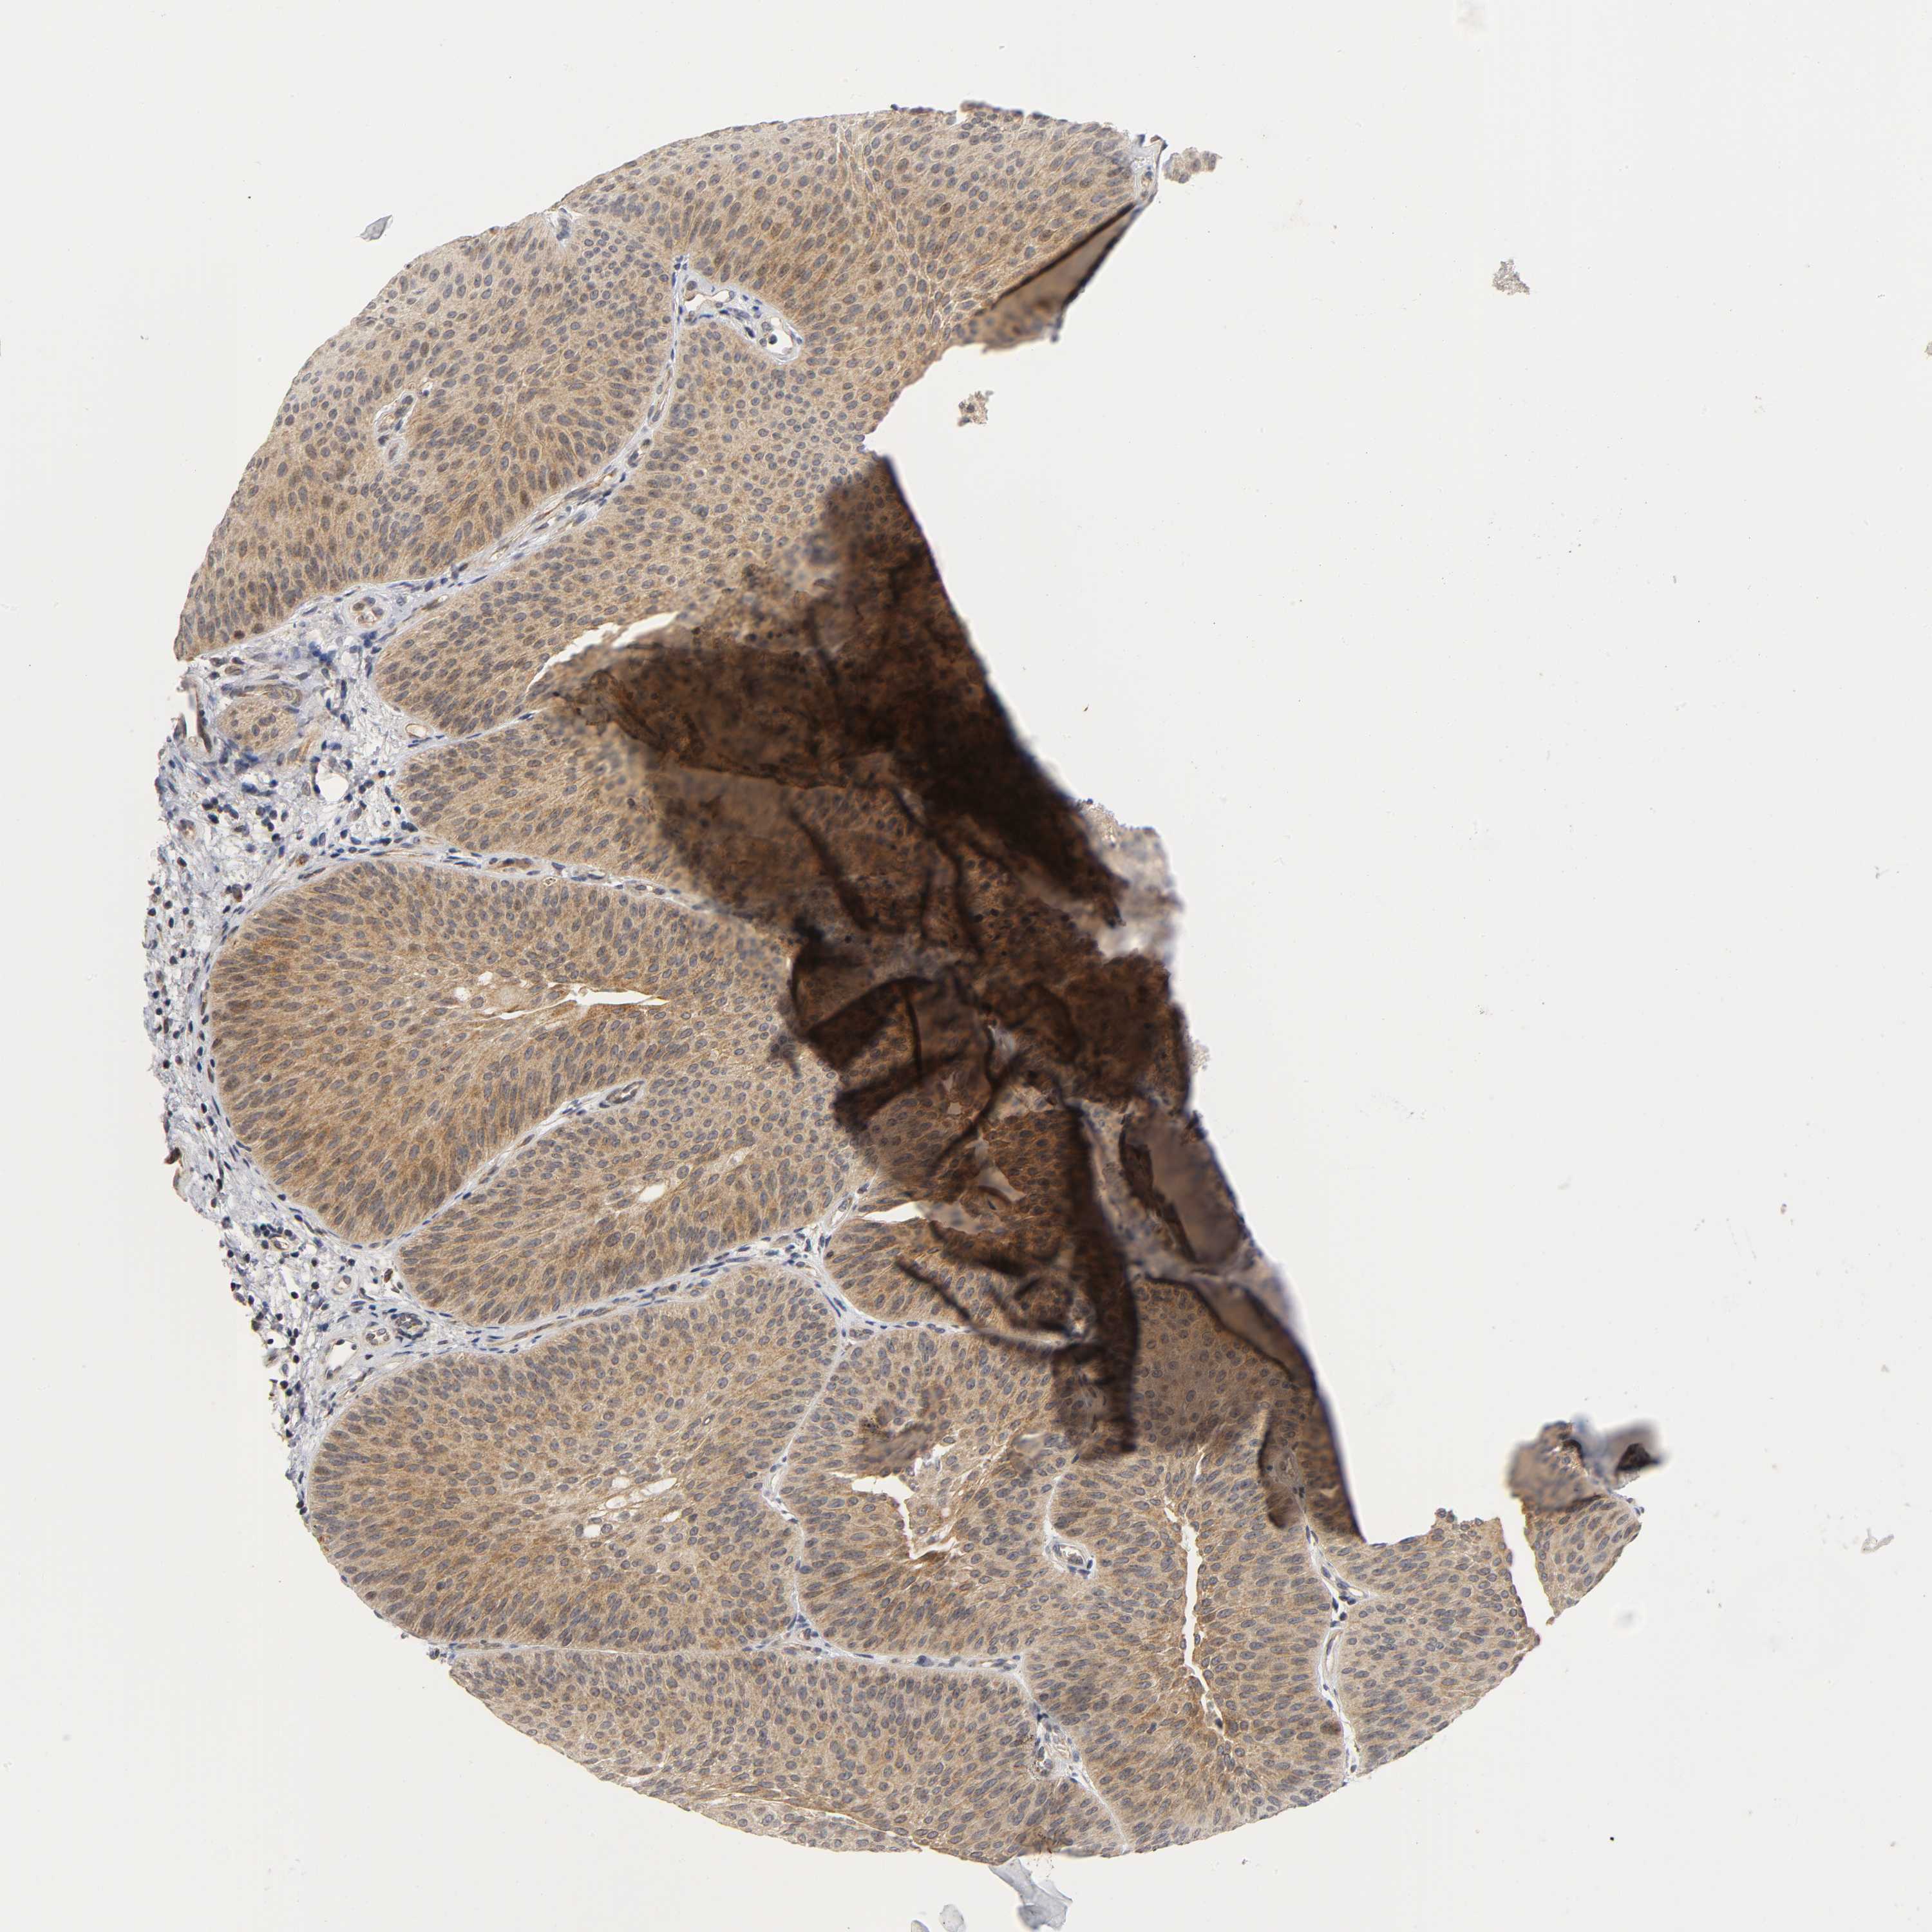

UROTHELIAL CANCER - Protein expressioni

A mouse-over function shows sample information and annotation data. Click on an image to view it in a full screen mode. Samples can be filtered based on level of antibody staining by selecting one or several of the following categories: high, medium, low and not detected. The assay and annotation is described here.

Antibody stainingi

Antibody staining in the annotated cell types in the current human tissue is reported as not detected, low, medium, or high, based on conventional immunohistochemistry profiling in selected tissues. This score is based on the combination of the staining intensity and fraction of stained cells.

Each image is clickable and will lead to virtual microscopy that enables deeper exploration of all samples and also displays staining intensity scores, fraction scores and subcellular localization as well as patient and tissue information for each sample.

Antibody HPA030278

Antibody CAB004511

Urothelial carcinoma, Low grade

Urothelial carcinoma, High grade